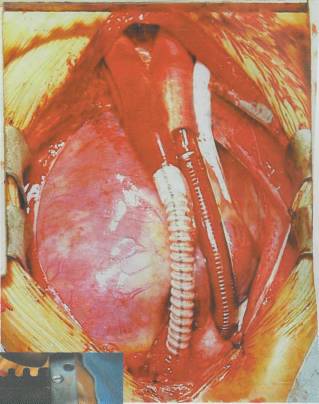

Kalp, en önemli organlardan biri. Koroner damarların tıkanmasına bağlı kalp kaslarının ölmesi, ve bunun sonucunda meydana gelen kalp krizi, dünyadaki en sık ölüm nedeni olarak gösteriliyor. Kalp hücreleri kendini yenileme yeteneğine sahip değil. Bu nedenle herhangi bir nedene bağlı olarak hücreler ölür ya da görev yapamazsa, yani hücreler kasılma yeteneğini kaybederlerse, kalp yetmezliği gelişiyor. Kalp yetmezliğinde vücuttaki kan yeterince pompalanamıyor ve organlar kansız kalıyor. Buna bağlı olarak da diğer organlarda yetmezlikler başlıyor. Milyonlarca insan kalp yetmezliğinin pençesinde ve nakil için uygun bir kalp bekliyor. Bu insanların fazla zamanı yok. Kanı pompalama

yeteneği olan yapay kalp cihazları nakil yapılana kadar geçen sürede hastalara zaman kazandırıyor. Ancak bu cihazların vücutta taşınması çok kolay değil. Enerjiyi aldıkları piller vücut dışında bulunuyor. Hastaların mutlaka yedek pillerle dolaşmaları gerekiyor. Yapay kalp cihazları yabancı cisim oldukları için, kan bunun içinden geçerken pıhtılaşabiliyor. Bunu engellemek için sürekli kanı sulandıran ilaçların alınması gerekiyor.

Son yıllarda kalp yetmezliğinin tedavisinde cihazlar yerine kalp kası hücrelerinin kullanılması gündeme geldi. Kemik ili

tedavi sürecini beklemek için zamanları olmuyor. Hücre ya da doku nakli sonrasında bu hücrelerin hedef bölgeye giderek burada çoğalmaları ve hasarlı hücrelerin yerini almaları uzun bir süreç gerektirebilir. Sonuçların alınması için belirli süre gerektiren bu ve benzeri tedavilerin, kalbin tamamının hasarlı olduğu durumlarda kullanılmaları pratikte mümkün olmayabilir. Böyle durumlarda organın tamamının en kısa sürede değiştirilmesi gerekir. Organ kaynaklarının son derece yetersiz olduğu günümüzde yapay olarak üretilecek organlar, en önemli umut kaynağı. Bilim adamları, yeni doğmuş farelerden alınan kalp hücrelerini kullanarak üç

ğinden alınan hücreler ya da embriyodaki kök hücreler kullanılarak kalp kası hücresi (kardiyomiyosit) oluştu-rulabiliyor. Kök hücreler birçok hücreye dönüşme yeteneğine sahip. İnsanın oluşumu aşamasındaki ilk hücreler olan embriyonel kök hücreler, kültürlerde çoğaltılarak özel büyüme faktörleri sayesinde kalp hücrelerine dönüştürülüyorlar. Bu hücreler farklı genetik yapıya sahip oldukları kişiye nakledildiklerinde bağışıklık sistemini harekete geçirebiliyor. Yapılan çalışmalar, kemik iliğinden alınan bazı hücrelerin de özel koşullarda kalp hücresine dönüşebileceğini gösterdi. Kişinin kendi kemik iliğinden alınacak olan hücrelerin genetik yapısı kalbindeki hücrelerle aynı olduğu için, bunların tedavi amaçlı kullanımı bağışıklık sistemi açısından sakınca yaratmıyor. Kemik iliği hücreleri özel kültürlerde kalp hücresine dönüşüyor. Bu hücreler belirli sayıya ulaştıktan sonra tekrar hastaya geri veriliyor. Bu hücreler dolaşım yoluyla kalbe giderek hasarlı bölgeye yerleşiyorlar. Hasarlı kalp hücreleri arasında yerini alan sağlıklı kalp hücreleri burada normal işlevlerini yerine getiriyor. Bu sayede kalp yetmezliği önlenebiliyor. Bu tür tedaviler henüz deneme aşamasında olmalarına karşın bilimadamları daha da ileri giderek kalp dokusunu vücut dışında oluşturmayı başardılar. Bir günlük yavru farelerin kalp hücrelerini alan bilimadamları bu hücreleri kollagen ve serum içeren bir ortama yerleştirdi

boyutlu kalp dokusu oluşturmayı başardılar. Fare kalp hücrelerinin, kollagen bir iskelet çevresinde toplanarak üremeleri sağlandı. Büyüme faktörleri sayesinde çoğaltılan hücreler kısa bir sürede birleşerek kollagen iskelet etrafında kenetlendi. Çoğalarak üç boyutlu şekil alan kalp hücreleri kasılma işlevini de yerine getiriyor.

Yapay kalp dokusu elde etme çalışmaları şimdi daha da ileri noktalara götürülüyor. Artık hedef kalp hücresi ya da kalp dokusu oluşturmak değil, üç boyutlu organ, yani yapay kalp yaratmak. Birçok kalp hastalığında, kişilerin uzun bir